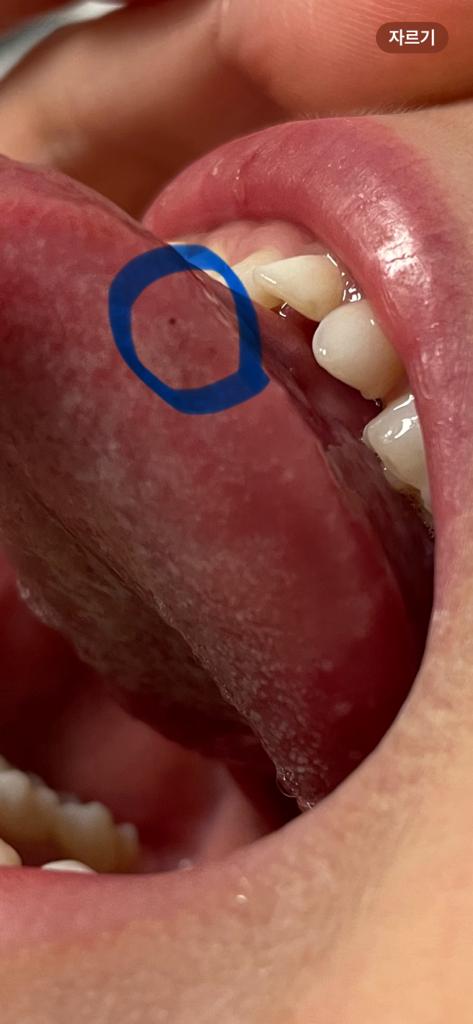

아이 혀에 작은점이 생겼는데 왜그럴까요?

아이 혓바닥 옆쪽에 작은점이 생겼었는데 몇달때 안사라지네요..처음에는 씹은건줄 알았는데 진하게 또다른 점이 생겼어요..ㅠㅠ점옆에 혀 색깔도 살짝 검은색을띄구요~사진에서는 잘 안보이는데 실제로보면 잘보여요😢왜그런걸까요?아프지는 않다는데..새로 생겨있는걸보니 걱정되네요.병원에 가봐야하나요?

• 안녕하세요. 서민석 의사입니다.

그걸 어떻게 발견하셨을까요? 혀에도 색소의 침착으로 점이 생길 수는 있습니다. 특별한 문제가 있는 것은 아니라서 그냥 놔두셔도 되구요.